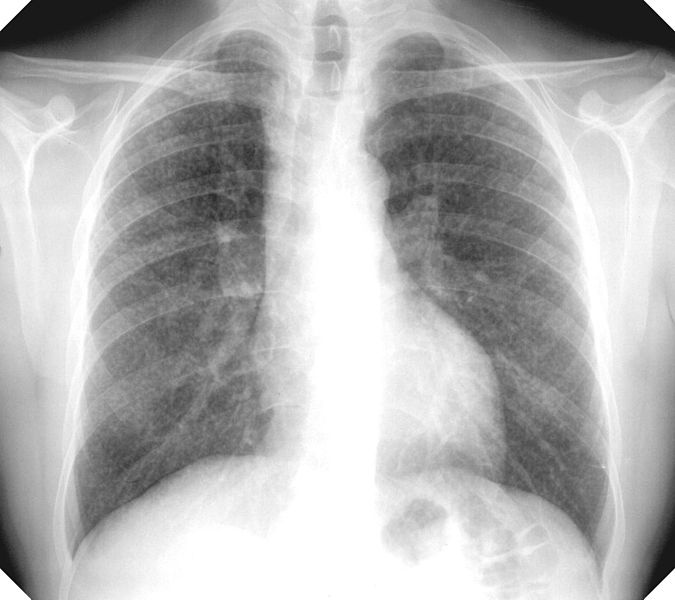

Number of fracking sites where the National Institute for Occupational Safety and Health (NIOSH) recently collected air samples to evaluate worker exposure to crystalline silica, which is present in the "frac sand" used in the natural gas extraction process and causes silicosis (shown in X-ray above), an incurable lung disease: 11

Percent of the tested fracking sites where workers' exposure to respirable crystalline silica exceed occupational health limits: 100

(Click on figure to go to source. X-ray showing lungs affected by silicosis by Gumersindorego via Wikipedia.)